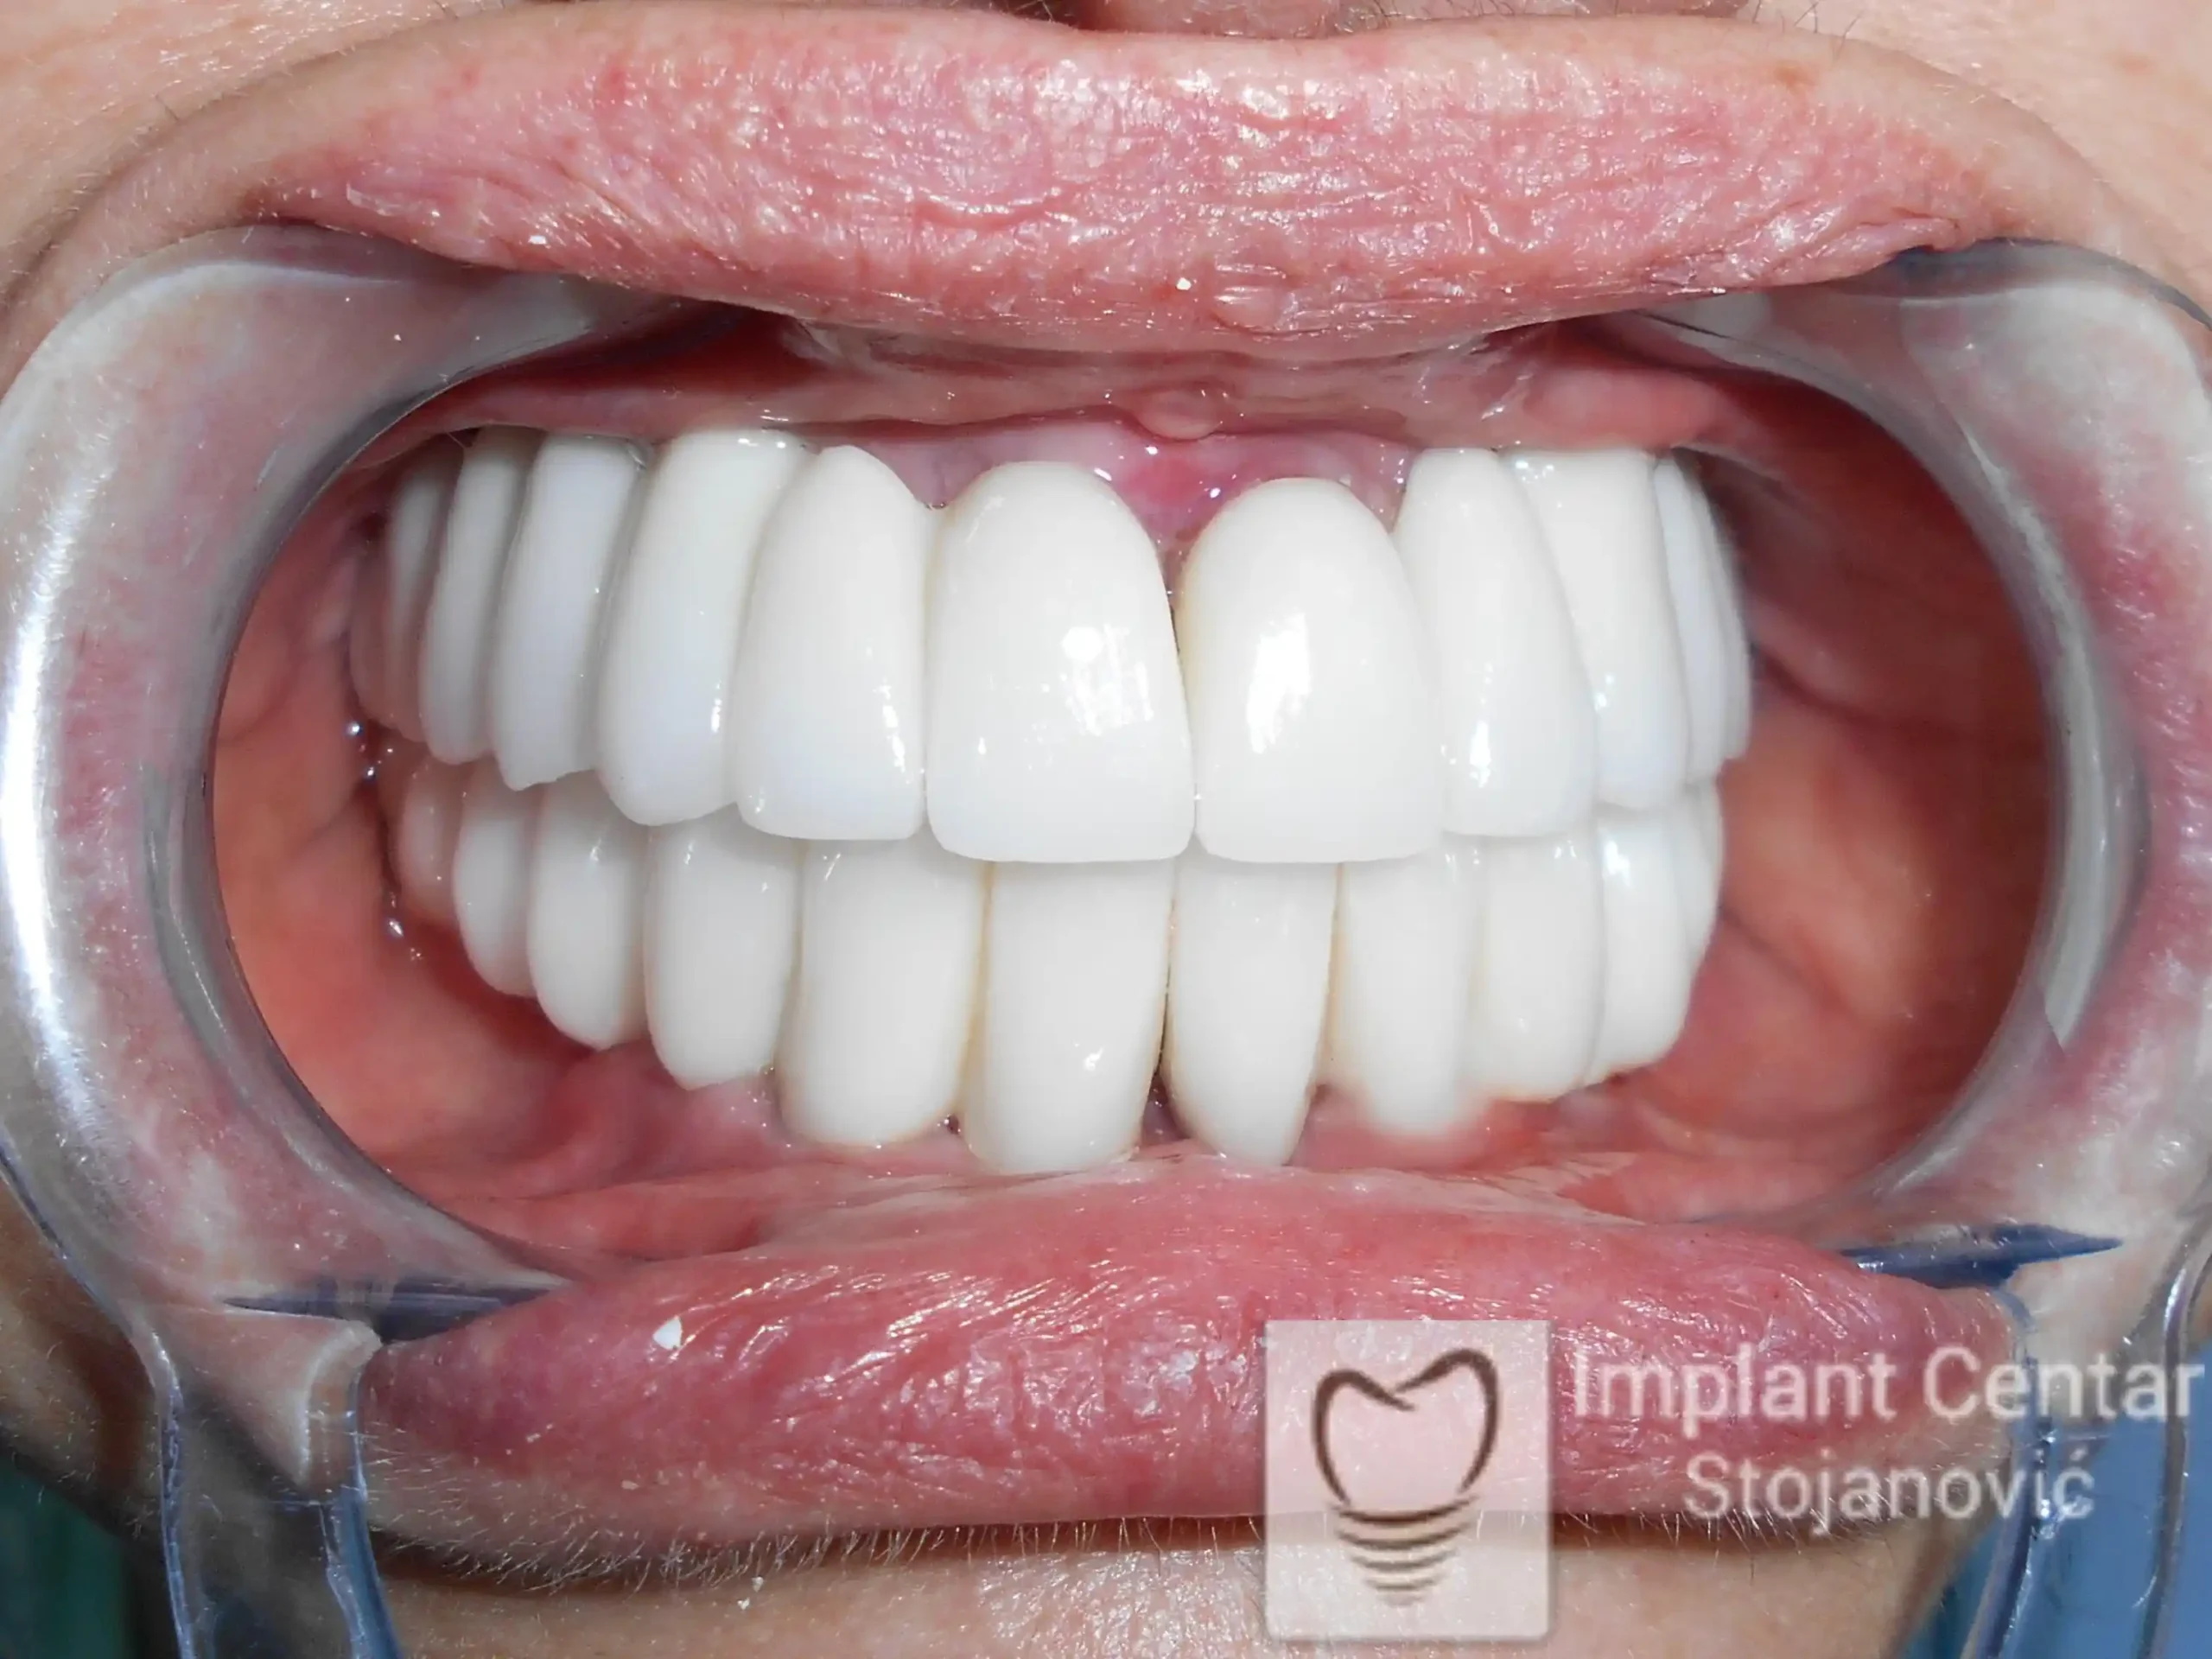

Nakon završetka procesa izrađeni su fiksni cirkonijum–keramički (bezmetalni) mostovi u obe vilice.

Rad je uspešno završen pre četiri godine, a rezultati su i dalje besprekorni – stabilni implantati, savršena funkcija i prirodan izgled osmeha.